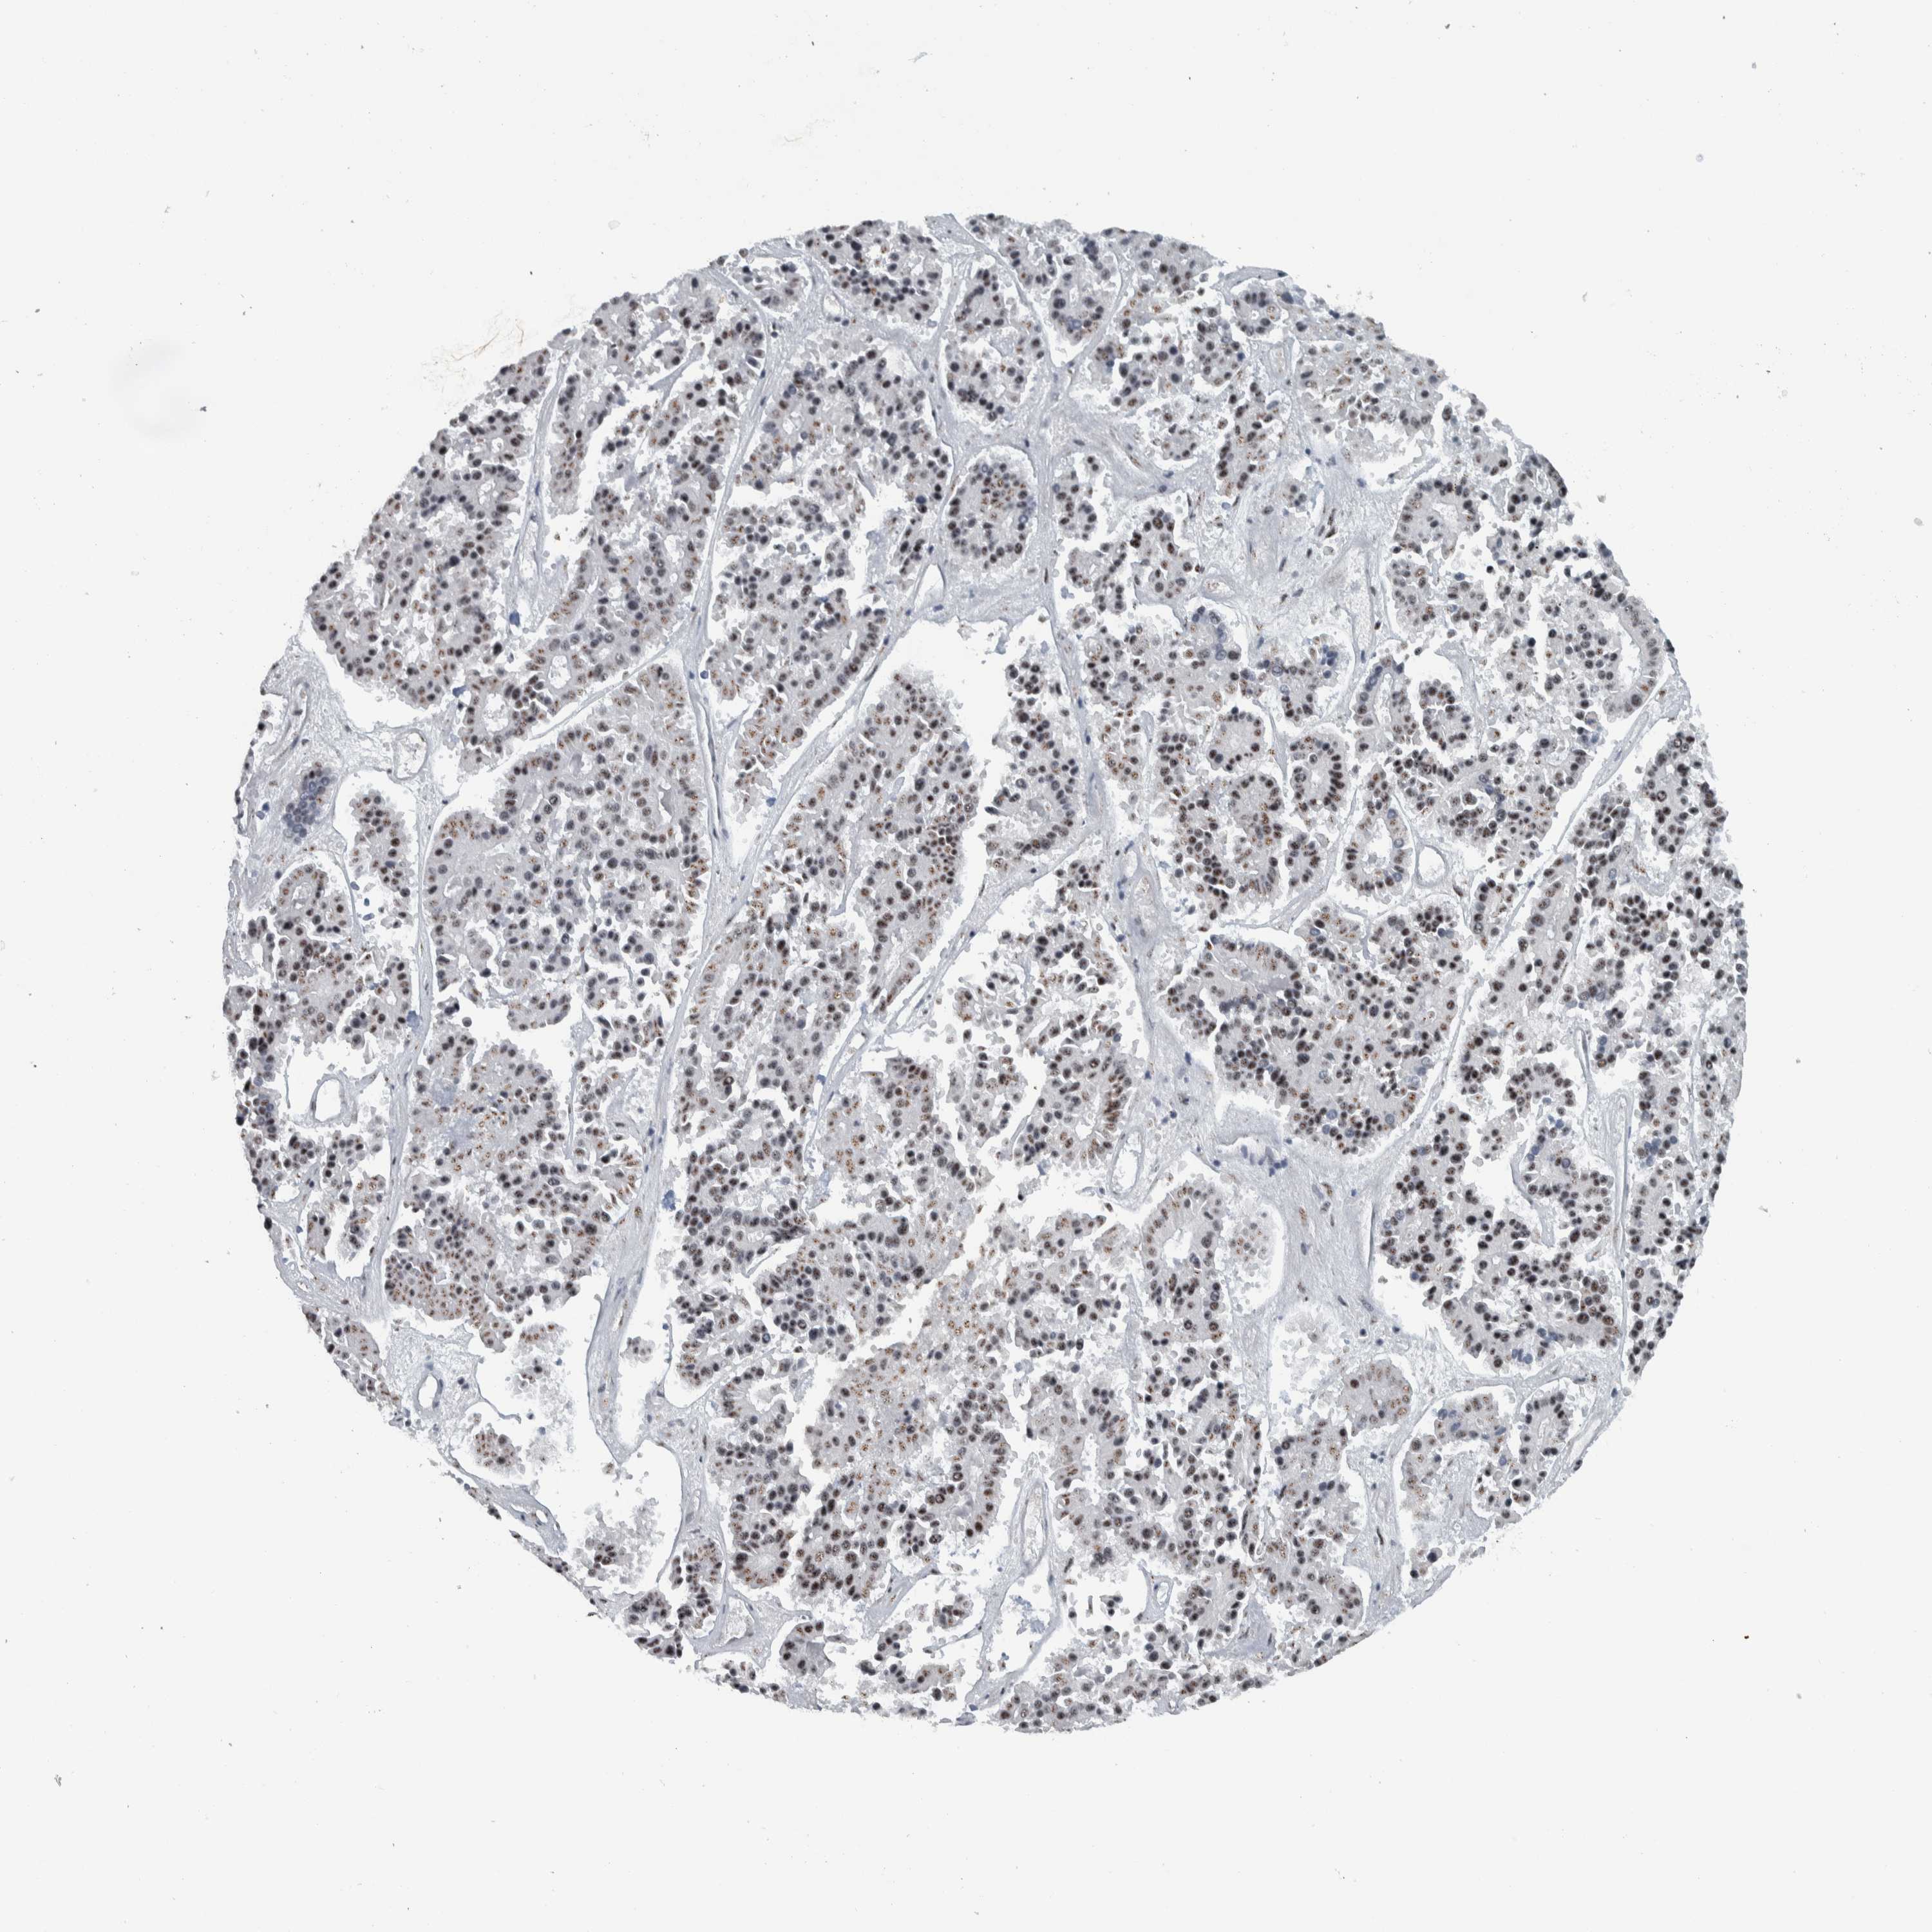

PANCREATIC CANCER - Protein expressioni

A mouse-over function shows sample information and annotation data. Click on an image to view it in a full screen mode. Samples can be filtered based on level of antibody staining by selecting one or several of the following categories: high, medium, low and not detected. The assay and annotation is described here.

Note that samples used for immunohistochemistry by the Human Protein Atlas do not correspond to samples in the TCGA dataset.

Antibody stainingi

Antibody staining in the annotated cell types in the current human tissue is reported as not detected, low, medium, or high, based on conventional immunohistochemistry profiling in selected tissues. This score is based on the combination of the staining intensity and fraction of stained cells.

Each image is clickable and will lead to virtual microscopy that enables deeper exploration of all samples and also displays staining intensity scores, fraction scores and subcellular localization as well as patient and tissue information for each sample.

Antibody HPA023535

Staining

High

Medium

Low

Not detected

Intensity

Strong

Moderate

Weak

Negative

Quantity

>75%

75%-25%

<25%

None

Location

Nuclear

Cytoplasmic/membranous

Cytoplasmic/membranous,nuclear

Adenocarcinoma, NOS